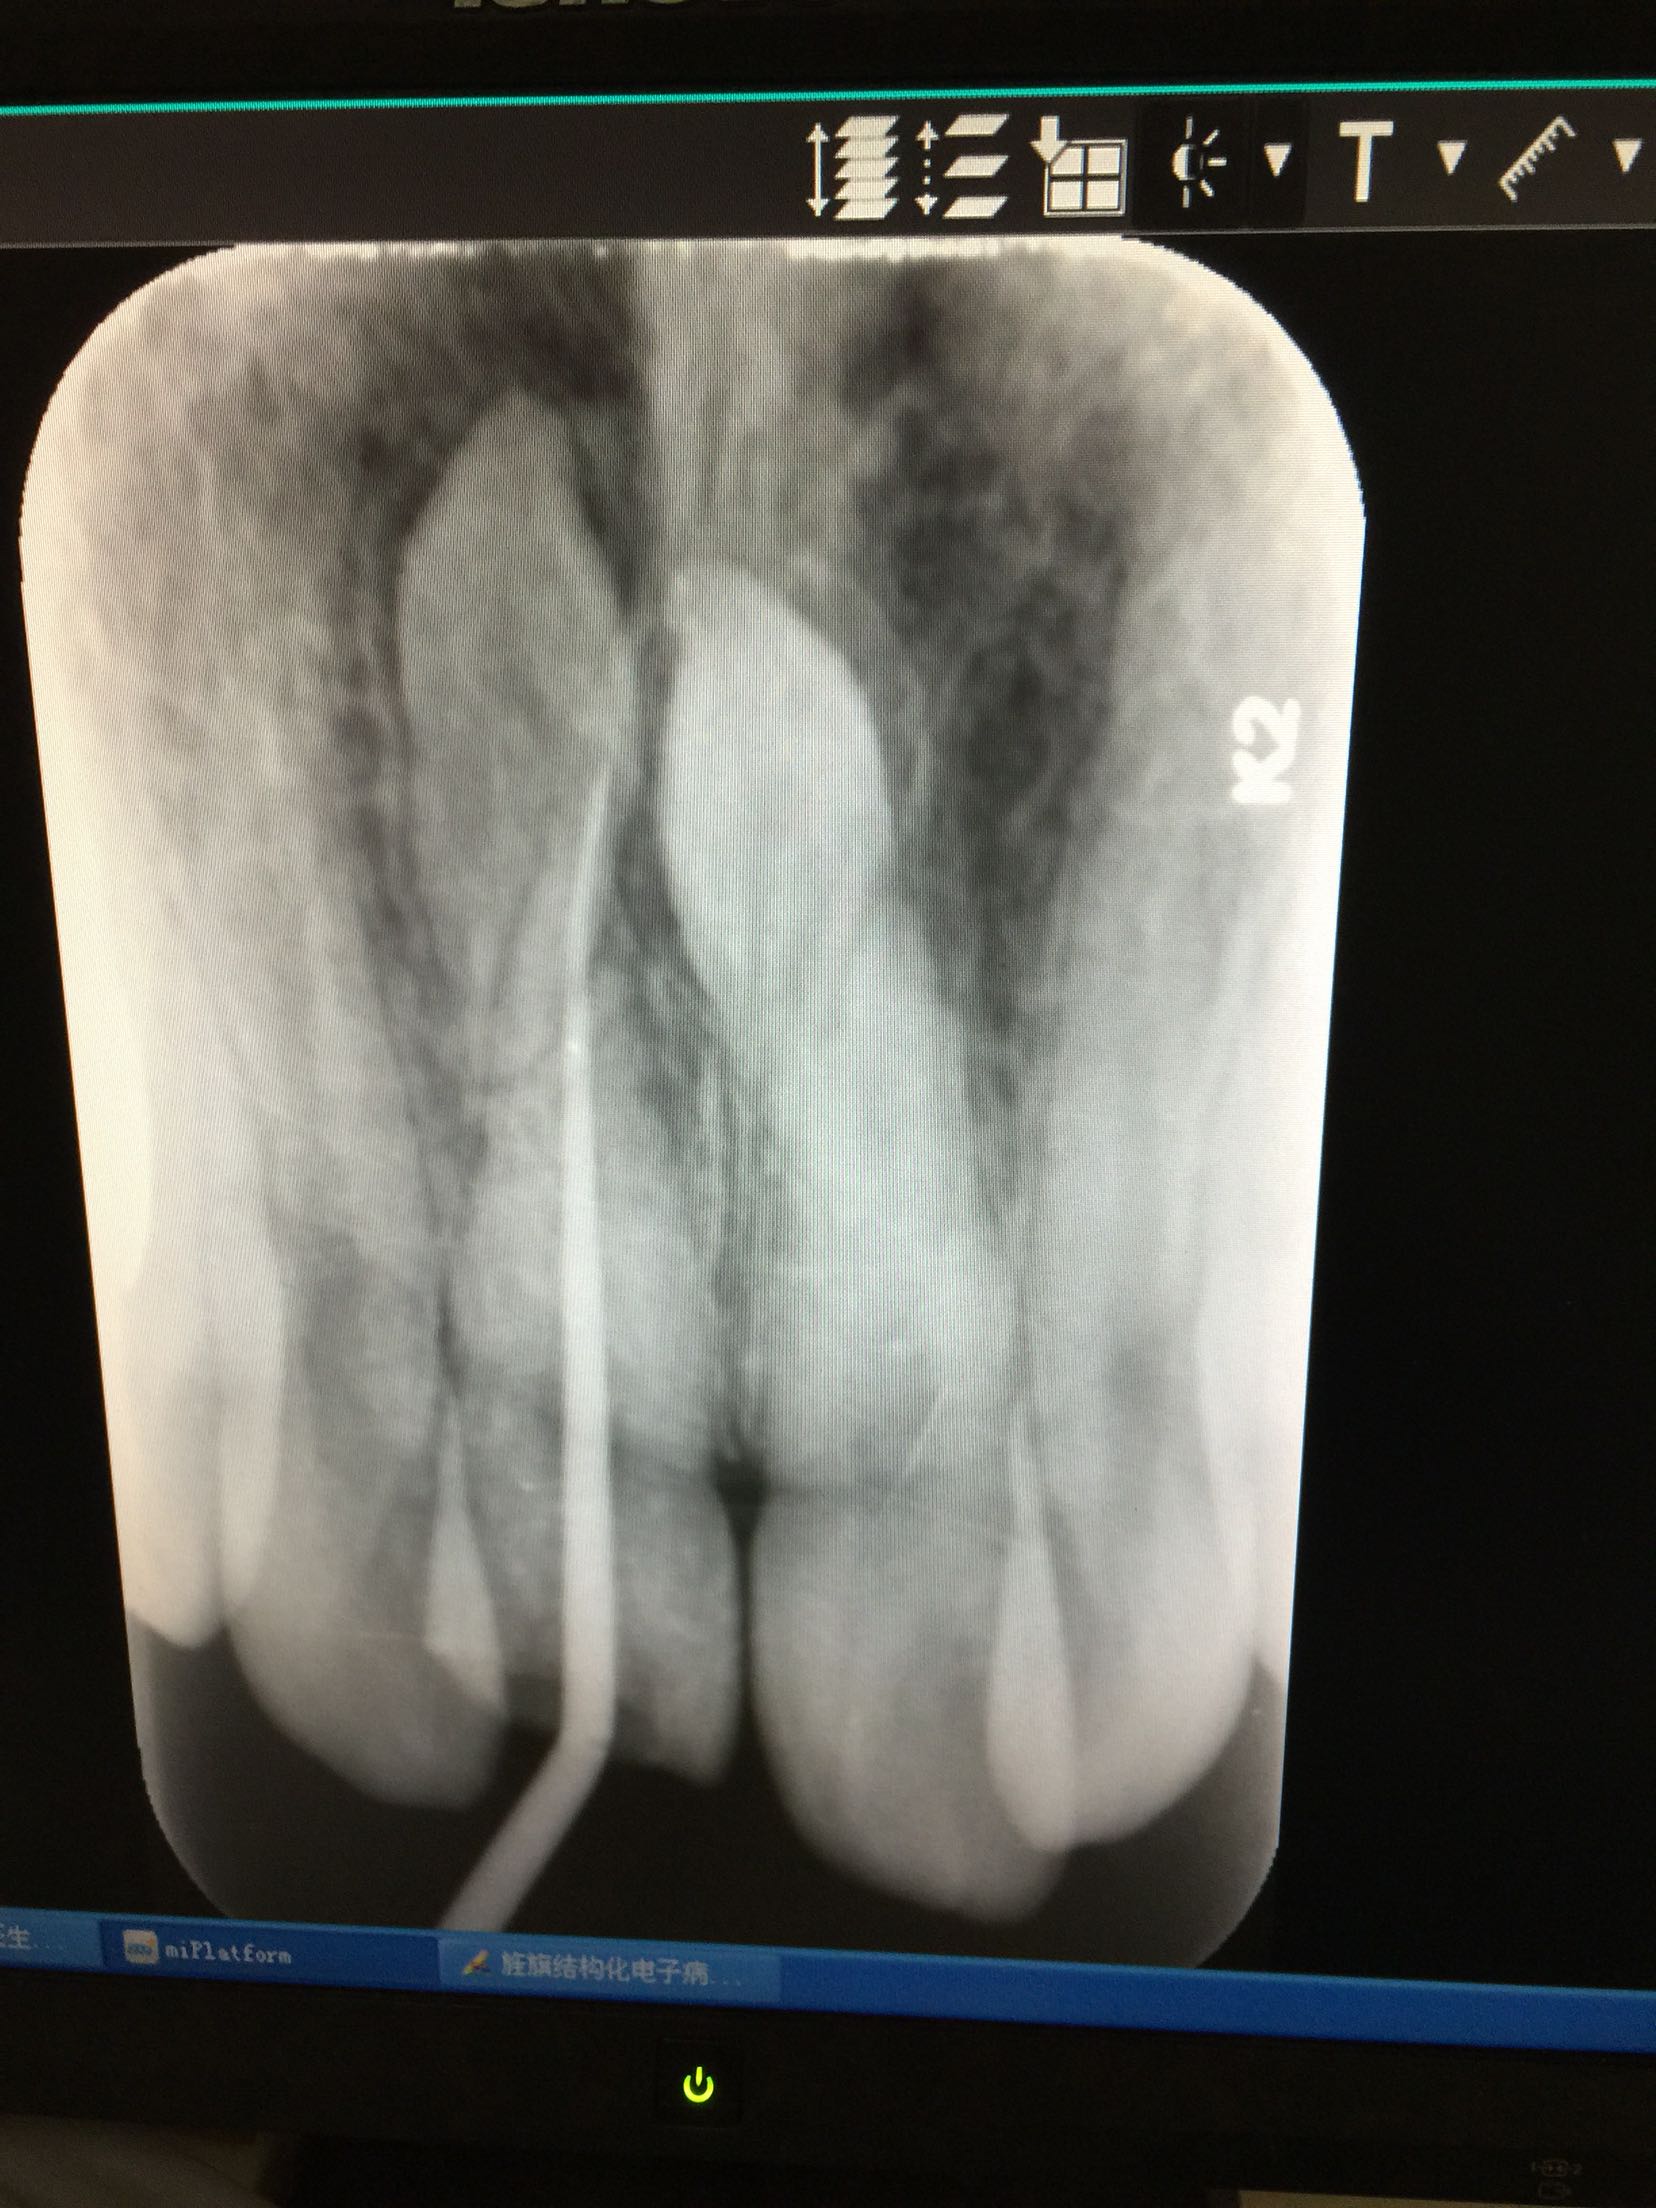

检查:全口卫生好,牙龈正常无退缩。11牙牙冠釉质牙本质折断,累及整个切缘,仅余留颈1/3,断面位于龈上4mm,可见白色暂补料,牙齿颜色正常,叩痛+,冷+,不松,牙髓电活力测试无反应,咬合关系正常。 RVG示:11牙牙冠部分缺损,已累及髓腔,未行根管治疗,很尖区未见异常,11、21牙根尖可见两颗多生牙。

诊断:11牙冠折 治疗计划:11牙行根管治疗+树脂美容修复 治疗:碧蓝麻局部浸润,11牙开髓揭髓顶,牙髓摘除,测长,根管预备,冲洗,消毒,试尖,热充,暂封,约复诊。